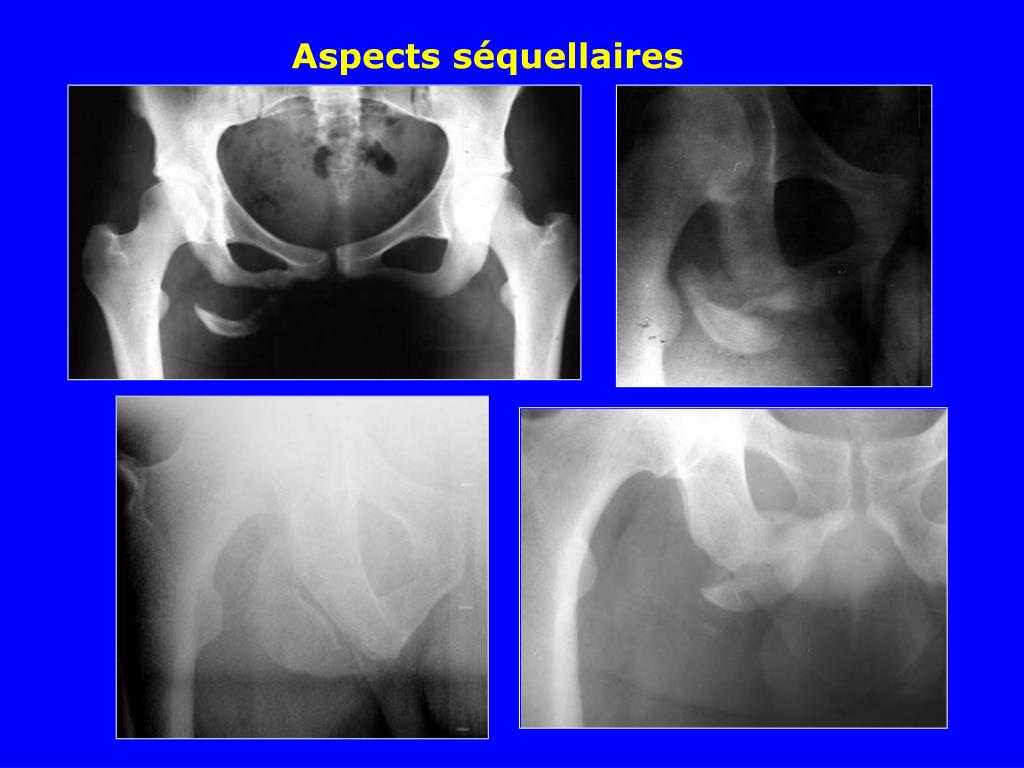

Fracture De Bassin . Le bassin est constitué de 3 structures osseuses : Dans cet article, on vous dit tout sur les fractures du bassin. Les fractures du bassin du sujet mûr, touchant plus volontiers les femmes, en raison de l'ostéoporose, et qui. Accident de voiture, de deux roues, chute violente, ou simplement de sa. L’iliaque, le sacrum et le pubis. Une rupture osseuse très douloureuse. Définition et types de fracture du bassin. Les fractures du bassin constituent la 3ème cause de mortalité lors d’accidents de la voie publique et ne sont précédées que par les traumatismes. | quelles sont les causes d’une fracture du bassin ? Il existe trois grandes catégories de fractures du bassin suivant le contexte : | quels sont les symptômes d’une fracture du bassin ?

| quelles sont les causes d’une fracture du bassin ? Les fractures du bassin constituent la 3ème cause de mortalité lors d’accidents de la voie publique et ne sont précédées que par les traumatismes. Le bassin est constitué de 3 structures osseuses : Une rupture osseuse très douloureuse. Les fractures du bassin du sujet mûr, touchant plus volontiers les femmes, en raison de l'ostéoporose, et qui. Définition et types de fracture du bassin. | quels sont les symptômes d’une fracture du bassin ? Accident de voiture, de deux roues, chute violente, ou simplement de sa. Il existe trois grandes catégories de fractures du bassin suivant le contexte : Dans cet article, on vous dit tout sur les fractures du bassin.

Fracture De Bassin Les fractures du bassin constituent la 3ème cause de mortalité lors d’accidents de la voie publique et ne sont précédées que par les traumatismes. Accident de voiture, de deux roues, chute violente, ou simplement de sa. | quels sont les symptômes d’une fracture du bassin ? Le bassin est constitué de 3 structures osseuses : Dans cet article, on vous dit tout sur les fractures du bassin. L’iliaque, le sacrum et le pubis. | quelles sont les causes d’une fracture du bassin ? Il existe trois grandes catégories de fractures du bassin suivant le contexte : Les fractures du bassin constituent la 3ème cause de mortalité lors d’accidents de la voie publique et ne sont précédées que par les traumatismes. Les fractures du bassin du sujet mûr, touchant plus volontiers les femmes, en raison de l'ostéoporose, et qui. Définition et types de fracture du bassin. Une rupture osseuse très douloureuse.